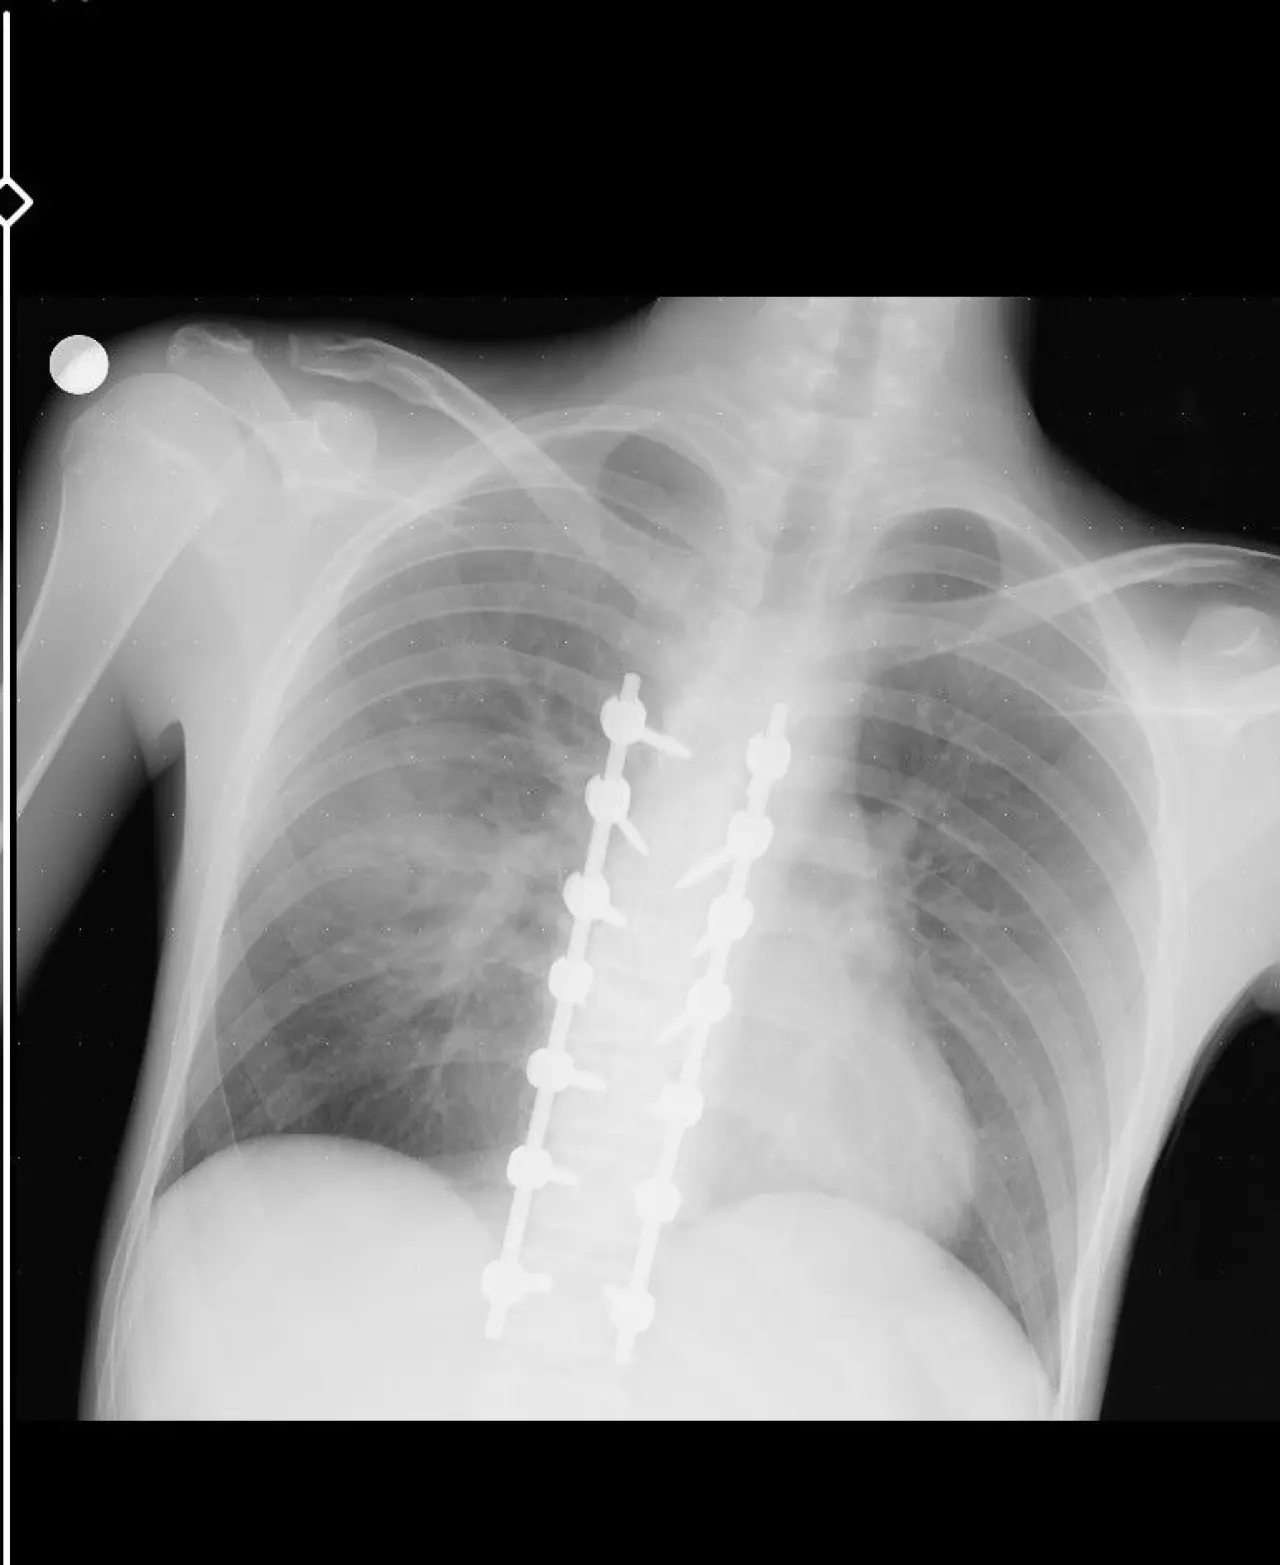

Motosiklet kazası sonrası oğlunun yüzünde ve vücudunda birçok kırık olduğunu dile getiren baba, “Yüz, çene, burun ve elmacık kemiklerinde parçalı kırıklar var. Omuriliğinde yedi kemiği platinle bağladılar, 14 civata var. Fakat hayatta, sağlıklı ve yanımızda. En önemlisi bu. Kask ve koruyucu ekipman olmasaydı, belki oğlum bugün hayatta olmayacaktı,” şeklinde konuştu.